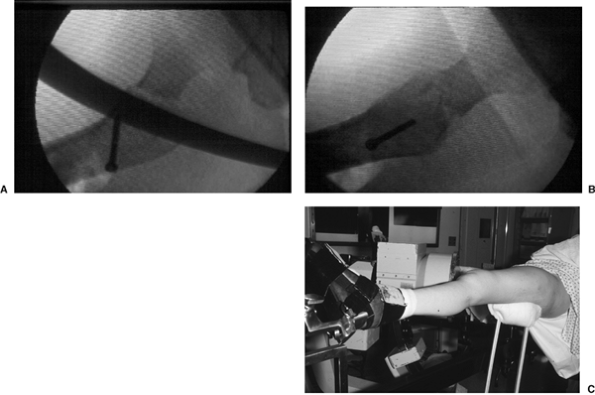

patient is positioned supine on a fracture table, with care taken to

pad and protect the labia or scrotum against the peroneal post. Once

the patient is properly positioned, a mobile c-arm intensifier is

positioned to allow visualization of the hip in AP and lateral planes.

Most intertrochanteric hip fractures can be reduced using gentle

longitudinal traction with the leg externally rotated followed by

varying degrees of internal rotation. The uninvolved leg must be

positioned so that it does not block positioning of the image

intensifier for a lateral view (Fig. 16.4).

before prepping the patient and be certain that nonobstructive,

biplanar, radiographic visualization of the entire proximal femur,

including the hip joint, is obtainable (Fig. 16.5). Inadequate visualization of the entire proximal femur can result in technical errors, such as inappropriate lag screw

![]() |

Figure 16.3. Use of internal rotation with gentle traction to evaluate a right, proximal, femur fracture.

Figure 16.4.

Patient positioning for stabilization of a left intertrochanteric fracture with the uninvolved leg flexed, abducted, and externally rotated. |

Figure 16.5. Positioning of the image intensifier for (A) AP and (B) lateral radiographic views. C. AP and and (D) lateral radiographs of a reduced intertrochanteric fracture prior to patient draping.